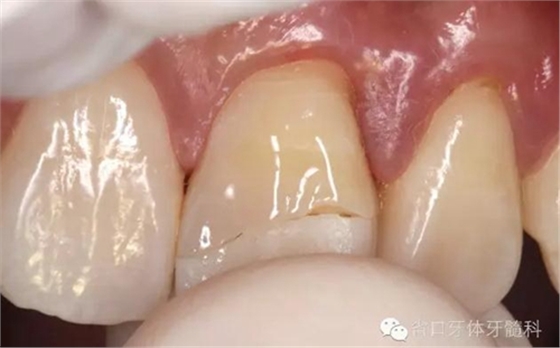

口內(nèi)檢查:21切1/3-1/2折斷,髓腔暴露,探痛明顯

近中鄰面探及齲損,松-,叩+,齦緣輕度紅腫,探及齦下結(jié)石。

術(shù)前口內(nèi)照

斷冠

折斷之牙體嚴(yán)重脫水,呈白堊色,斷端對(duì)位后吻合度較好,僅少許牙體缺損。